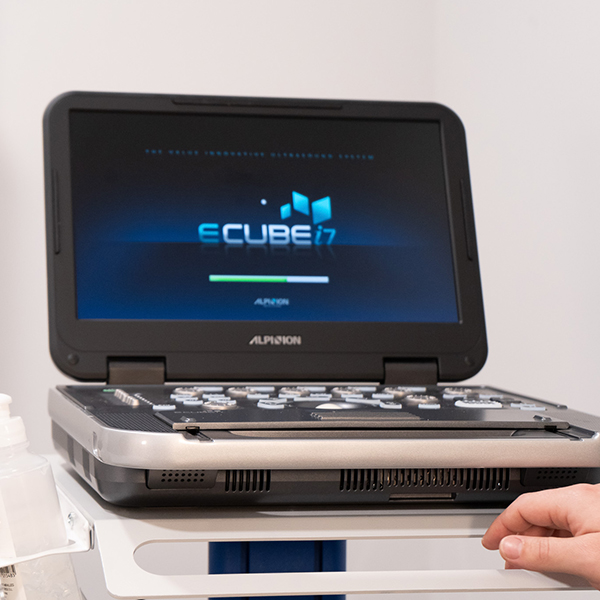

Alpinion i7

Valoración y tratamiento mediante ecografía Alpinion i7.